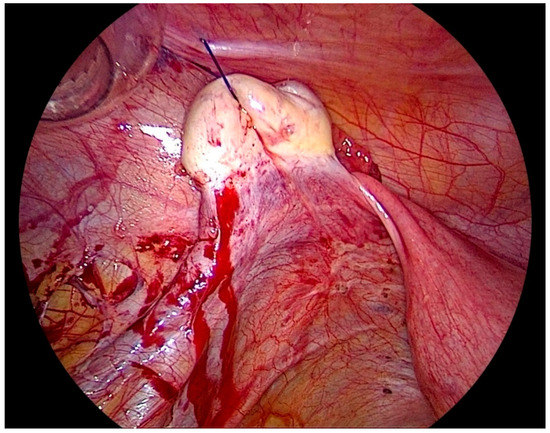

After gaining access to the peritoneal cavity laparoscopically (Figure 1), the cavity is thoroughly investigated for endometriotic cysts, spots, and adhesions. If an endometriotic ovarian cyst is found, it is excised. If endometriotic spots or nodules are found underneath the ovary on the ovarian fossa, or uterosacral ligaments, the ipsilateral ovary is suspended to the anterior abdominal wall (Figure 2). A straight needle with a single monofilament non-absorbable thread is passed through the lower anterior abdominal wall. Prior to insertion of the needle, the inferior epigastric vessels should be located to avoid injury and hematoma formation. The needle is retrieved intra-corporeally by grasping it using a laparoscopic needle holder. It is then passed from the medial side of the ovary through the ovary into the abdominal wall close to the point where it was introduced. At this step also, it is essential to pay attention to the inferior epigastric vessels once more. The needle is then pulled out from the abdominal wall using a hemostat forceps. The two ends of the thread are tied extra-corporeally over a compressor gauze on the abdominal wall, with some tension, thus suspending the ovary to the abdominal wall with the medial side of the ovary apposed to the peritoneum of the anterior abdominal wall (Video S1).

Figure 2. Laparoscopic view of the lateral pelvic wall on the left side after ovariopexy with endometriosis easily visualized and accessible.